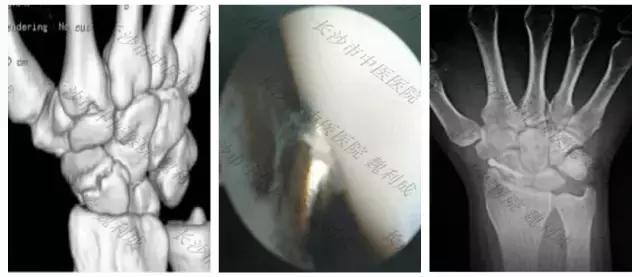

△手舟骨骨折(左图:术前三维CT示舟骨腰部骨折,中图:镜下复位内固定,右图:术后X线)